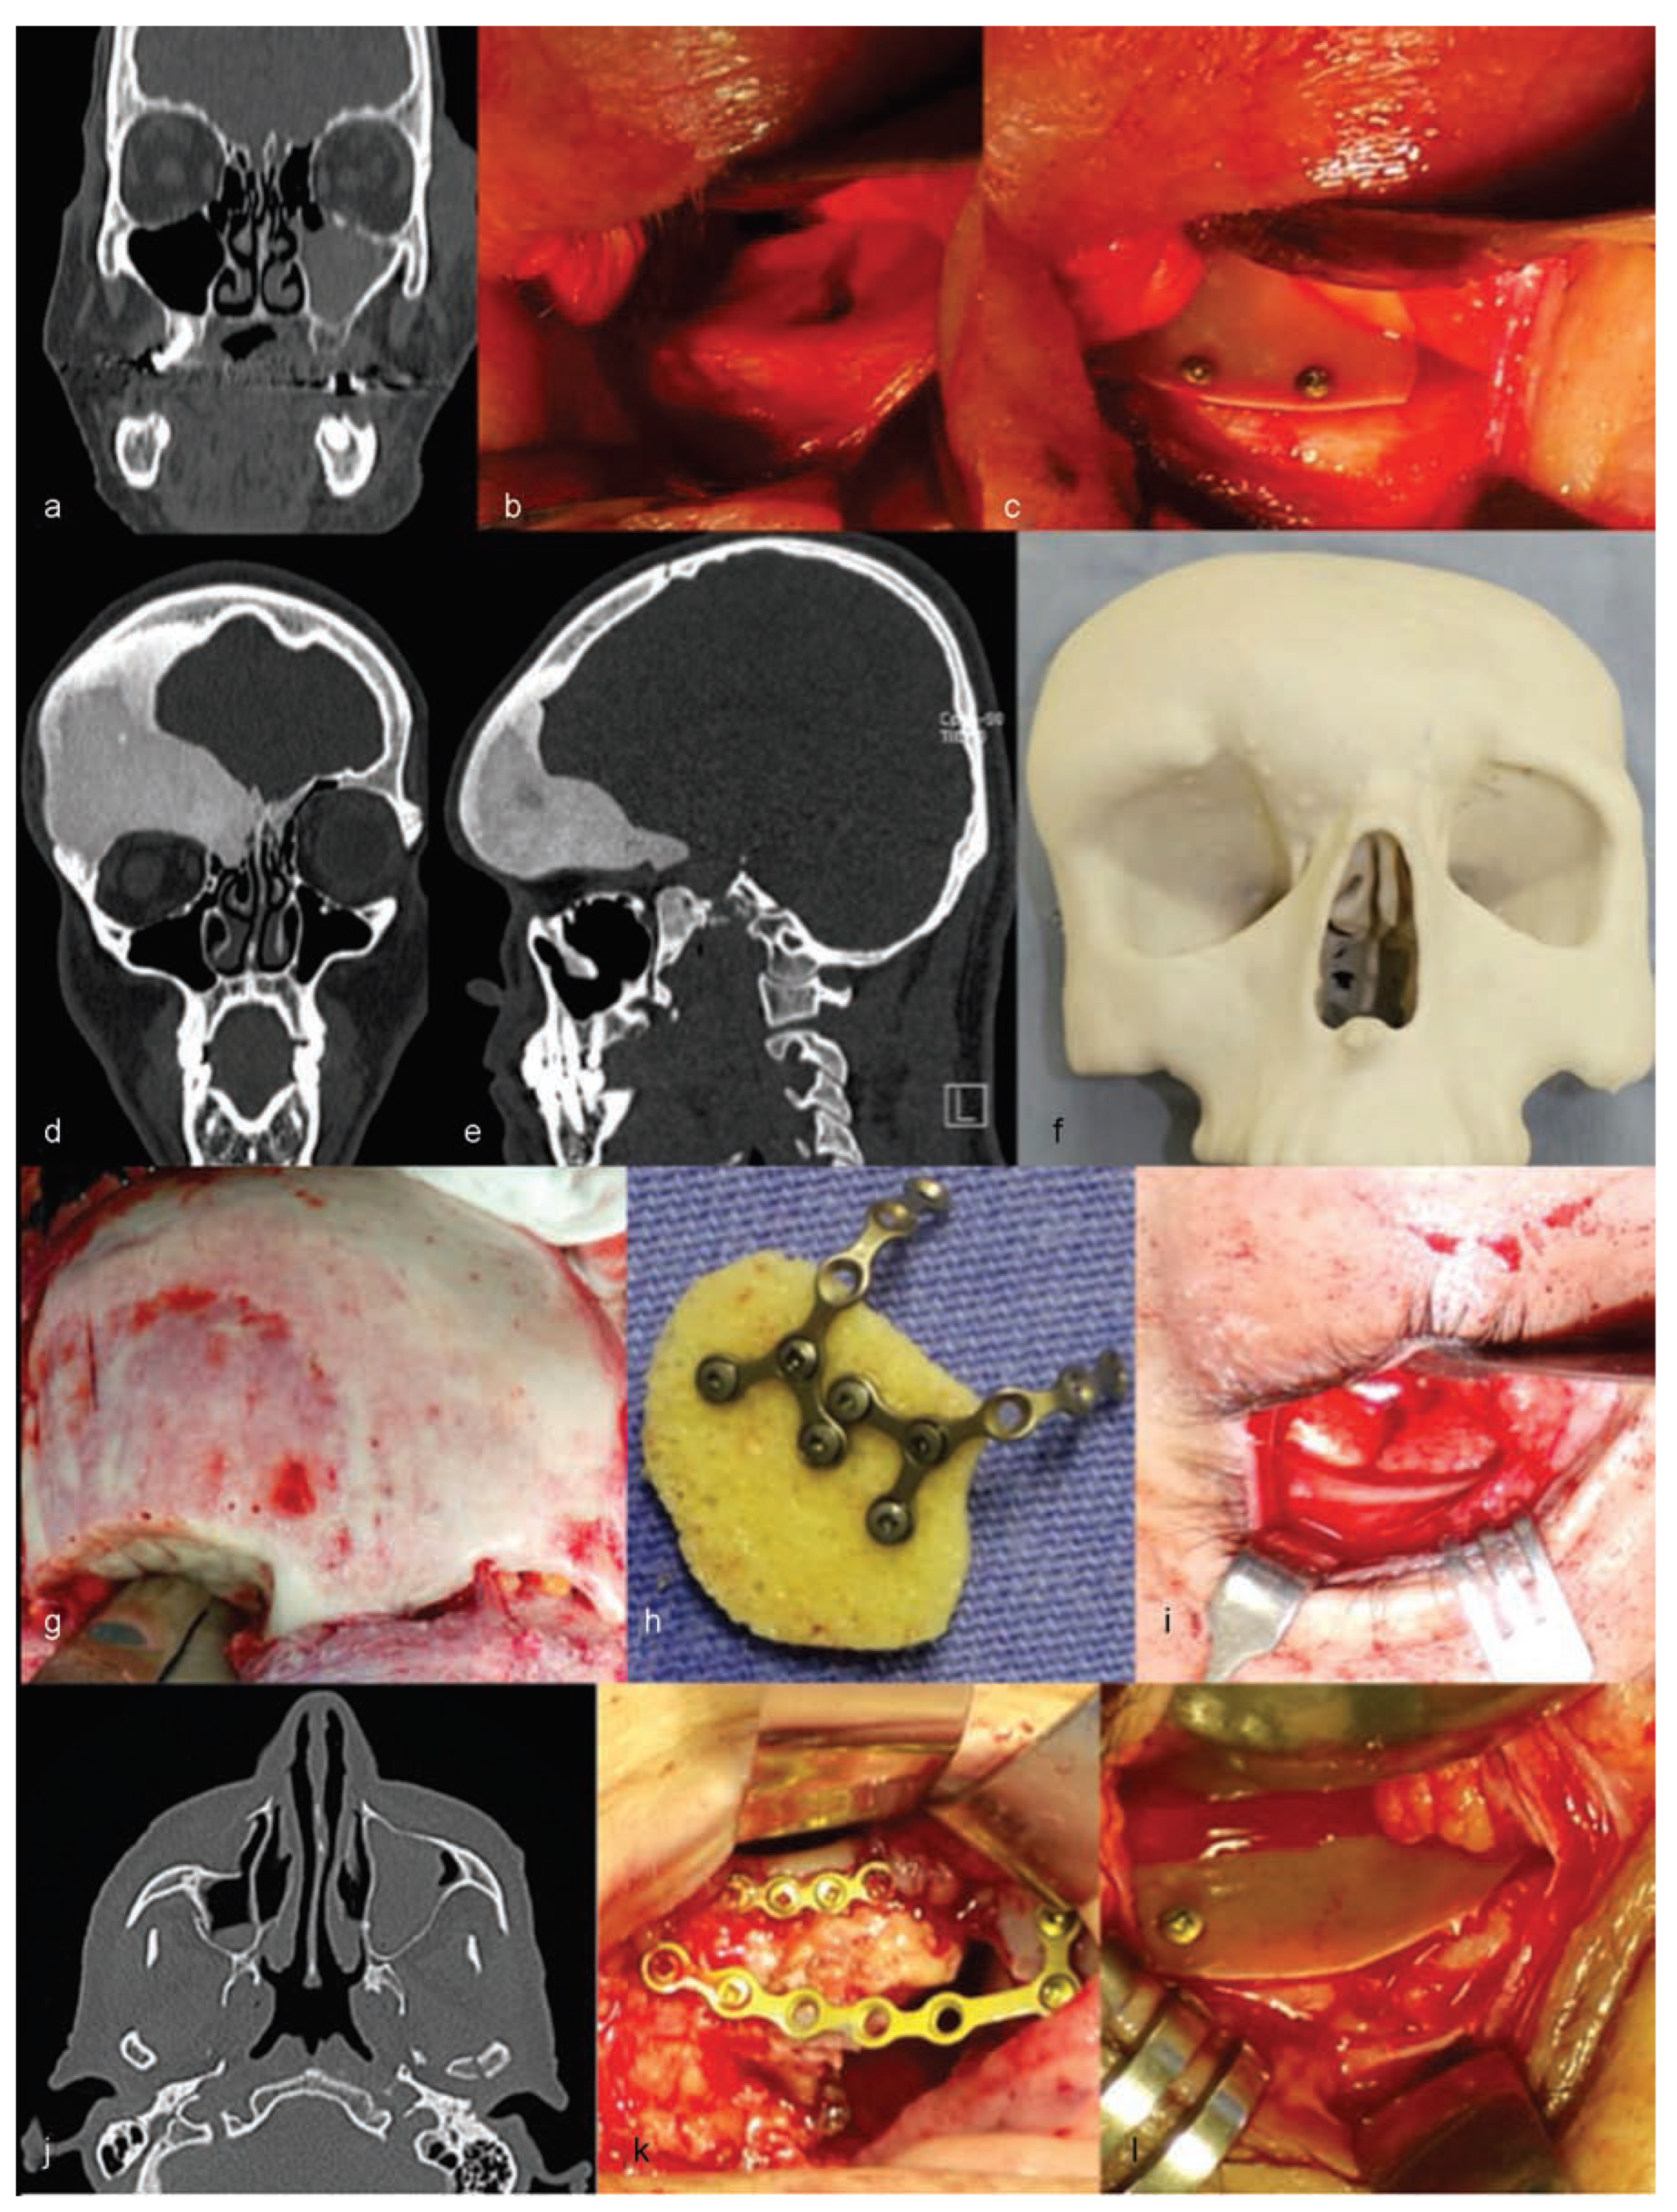

The authors are experienced with the use of castor oil polymer prostheses in several cases of trauma and surgery for camouflage deformities (Figure 1 and Figure 2).

Figure 1. Cases of patients treated with the use of castor oil polymer prosthesis I: (ac,jl) Orbital floor fractures. (di) Orbital deformity due to fibrous dysplasia.

Figure 2. Cases of patients treated with the use of castor oil polymer prosthesis II: (mo,su) Orbital medial wall fractures. (pr) Orbital floor fractures.